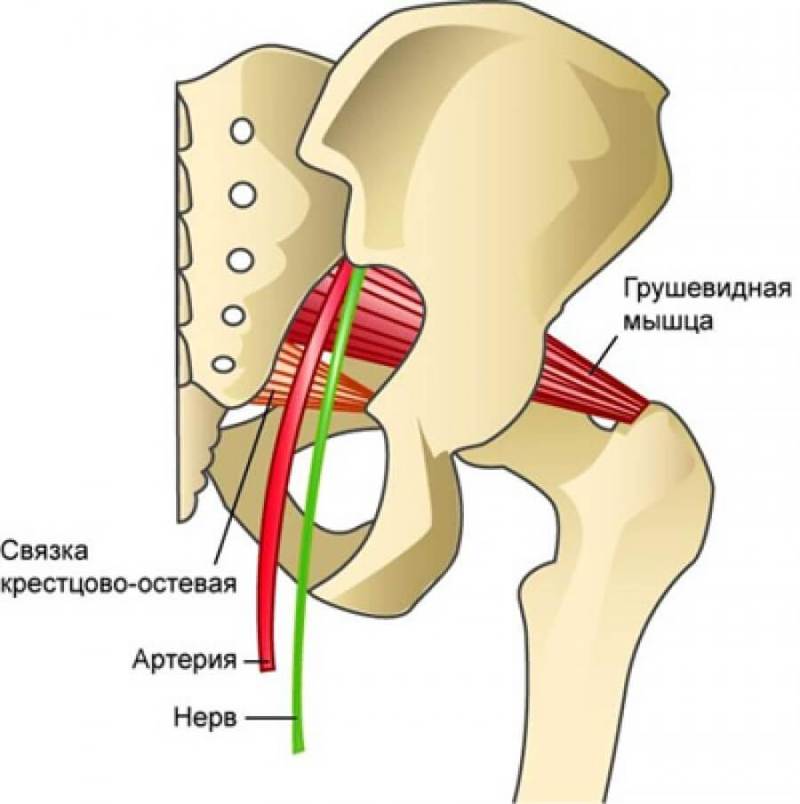

Анатомия и упражнения: Перекос таза и мышцы бедра